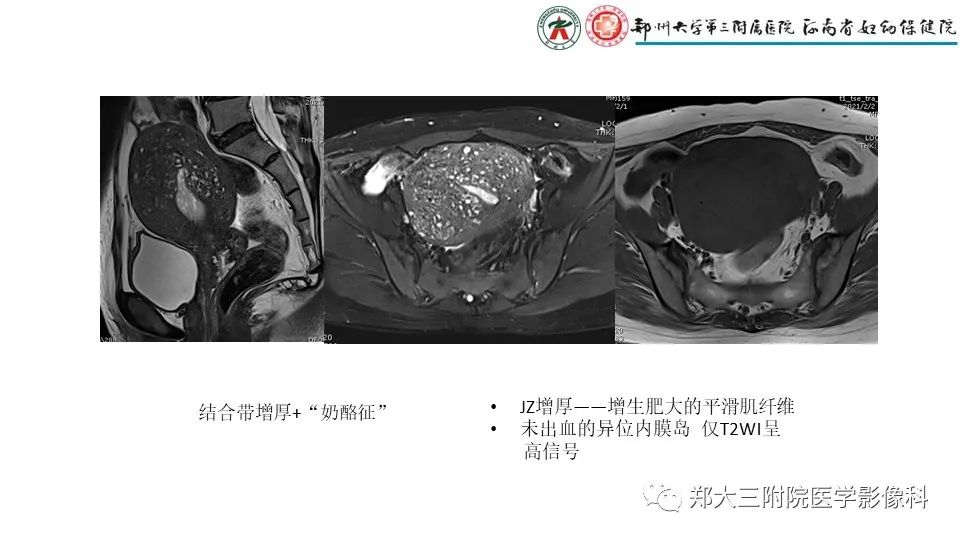

来源:郑大三附院医学影像科